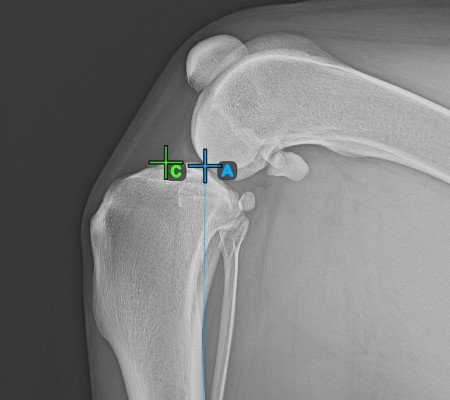

Sobald die Längsachse der Tibia bestimmt wurde, markieren Sie den vordersten Punkt des Tibiakopfes (Tibiaplateau).

Das Bild unten zeigt die übliche Platzierung des vordersten Punkts am Tibiaplateau.